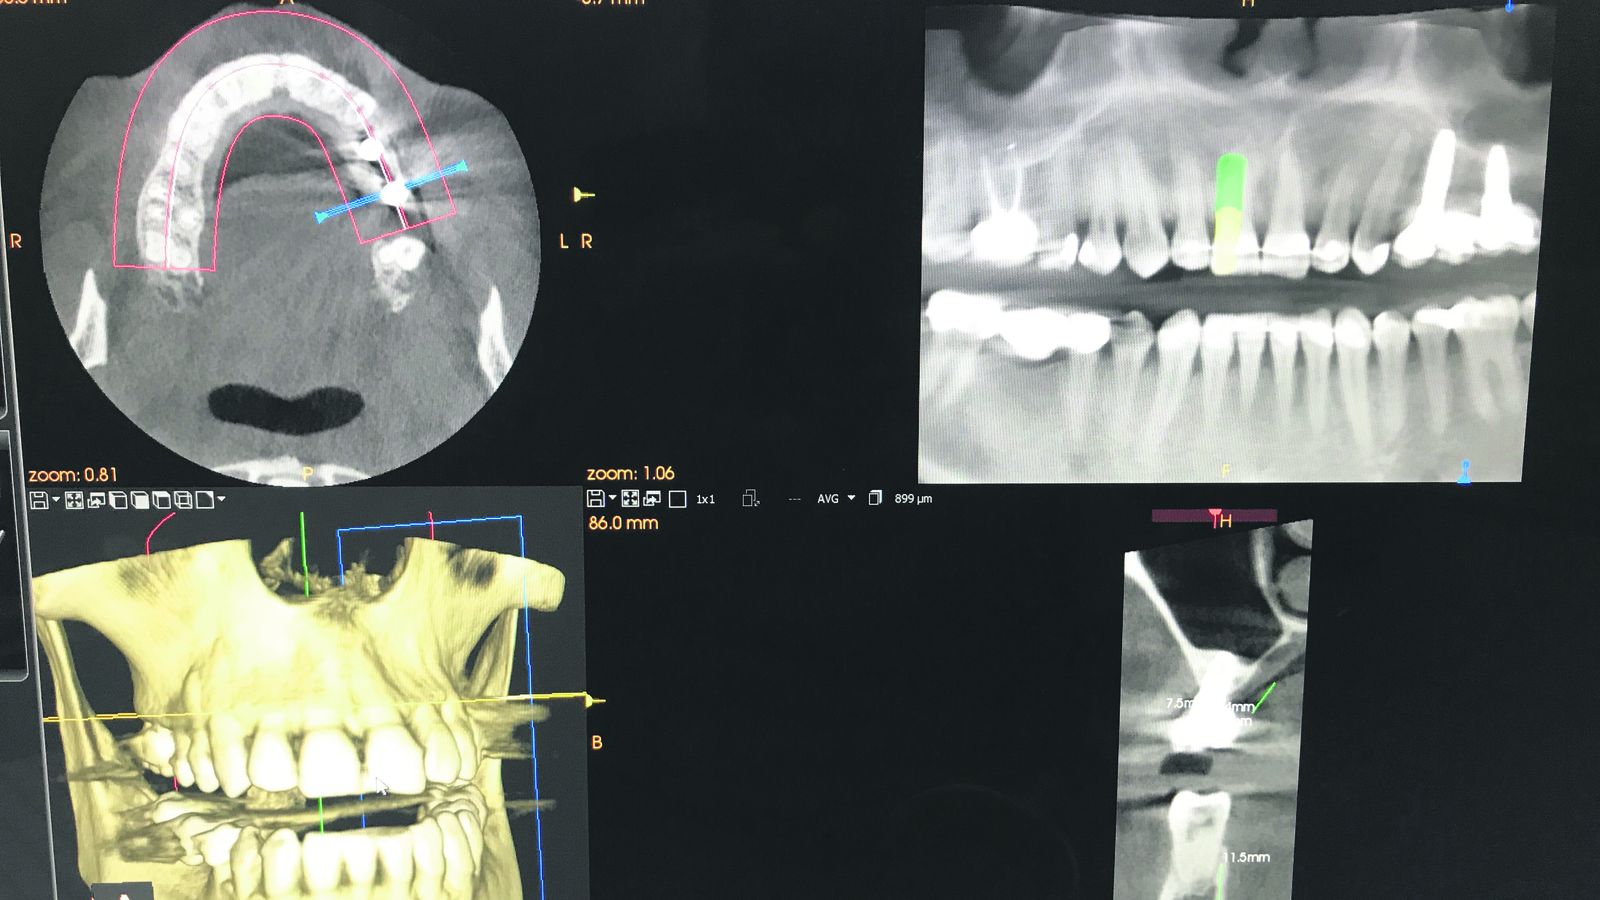

Conseguimos una sonrisa perfecta en cada paciente gracias al uso de aparatología medica de ultima generación. En nuestras instalaciones disponemos de SCANNER 3D, intraoral 3DSHAPE para escanear las coronas y enviarlas al laboratorio sin necesidad de introducir en la boca del paciente alginatos y silicona, evitando una mala experiencia para el paciente.

En nuestra clínica ofrecemos las técnicas menos invasivas y más modernas para que la colocación de implantes dentales sea sencilla, rápida y sin molestias. Es una inversión en calidad de vida y bienestar.

Para aquellos pacientes con miedo a la atención odontológica, con malas experiencias anteriores, con poca disponibilidad de tiempo o, simplemente, que se tengan que desplazar desde otras provincias o desde el extranjero, la Clínica Dental Copano utiliza nuevas técnicas de regeneración ósea, colocación de implantes y atornillado de dientes en el mismo día.

Los avances se han producido fundamentalmente en la utilización de la técnica en regeneración osea terapéutica del plasma rico en factores de crecimiento (PRGF®). Se trata de una tecnología biomédica mediante la cual se consigue estimular la regeneración de los tejidos concentrando factores de crecimiento y otras proteínas presentes en el plasma sanguíneo del propio paciente.

La tecnología (PRGF®) es pionera a nivel mundial en el uso de un plasma rico en plaquetas (PRP) en clínica.

Esta técnica asegura el éxito de la colocación de implantes, 6 meses después de la regeneración osea.